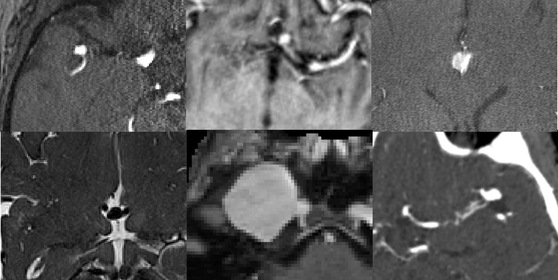

RSNA Intracranial Aneurysm Detection

Kaggle competition to identify and localize intracranial aneurysms using CTA, MRA, and MRI data. Built deep learning pipelines for 3D medical image analysis, leveraging spatial localization and vessel segmentation labels. Currently ranked in the [your percentile here] percentile on the ongoing leaderboard.

- Developed preprocessing and augmentation for multimodal series (CTA, MRA, T1/T2 MRI).

- Trained models for detection and localization across 13 anatomical sites.

- Integrated vessel segmentation for improved spatial accuracy.

Computer VisionMedical ImagingDeep LearningKaggle